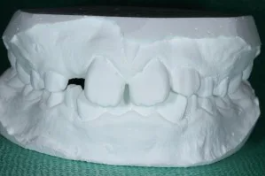

こちらはQくん。約2年前のかみ合わせはこちら。

ん?どこが悪い歯並びなの??と感じるお母さまも多いかもしれません。

これは『過蓋咬合(かがいこうごう)』という歯並びで、上の前歯が、下の前歯を大きく覆いかぶせてしまっています。

横から見ると、上と下の歯が全く当たっていないのがよくわかりますね。

これでは、お蕎麦がすすれない(;´∀`)